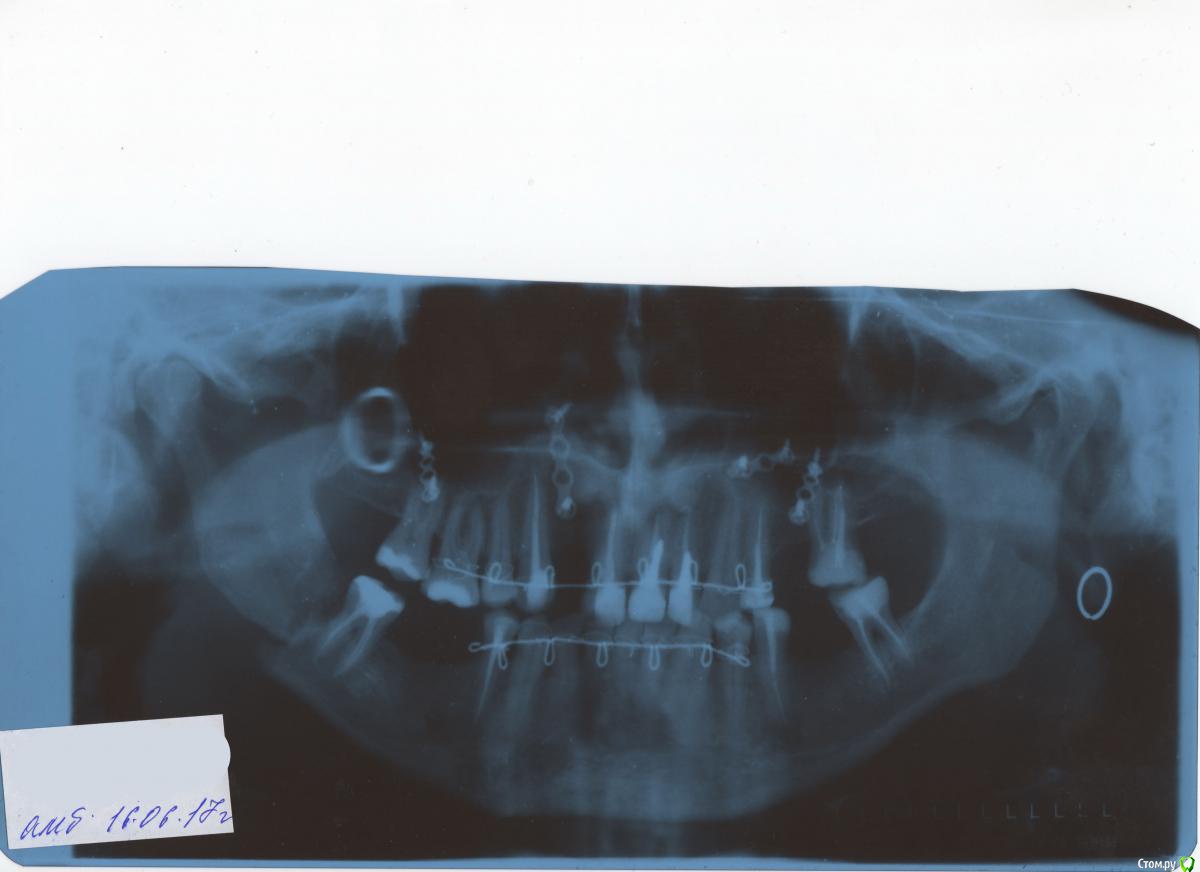

RomanRV41 Опубликовано 19 июня, 2017 Поделиться Опубликовано 19 июня, 2017 (изменено) Здравствуйте! 1 июня при удалении 4/8 зуба сломали челюсть. 7 июня сделали шинирование. Всё это время сильные боли, спать начал дней 7 назад и то не всегда( режущая резкая боль между подбородком и скулой.16 июня сделал снимок и врач сказал что всё идет норма и челюсть встанет на место. На сегодня чувствую гораздо лучше, отёк остался небольшой.Подскажите правильно ли такое лечение (переживаю правильно ли срастётся) или надо идти в ЧЛХ к другому врачу ставить пластину? Изменено 19 июня, 2017 пользователем RomanRV41 Ссылка на комментарий